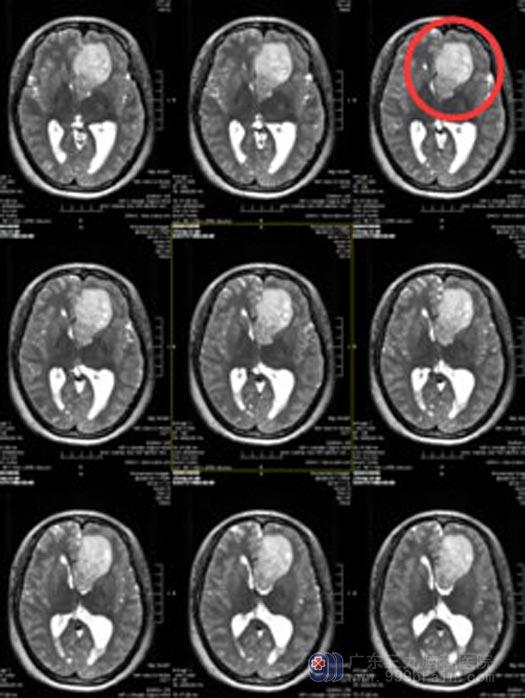

郑女士一周前开始出现头痛头晕,以额部疼痛明显,有时会伴有恶心症状。广东三九脑科医院头颅MR提示“左侧额叶胼胝体占位病变”。

手术前